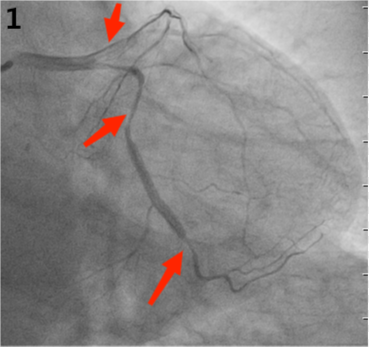

考虑血管存在痉挛,予以“硝酸异山梨酯注射2ml”冠脉内注入,复查造影示:LAD主支近段20%节段性狭窄,前向血流TIMI-3级;LAD中段70%左右节段性狭窄,前向血流TIMI-3级;LCX主支近段40%左右节段性狭窄,前向血流TIMI-3级。(图2)